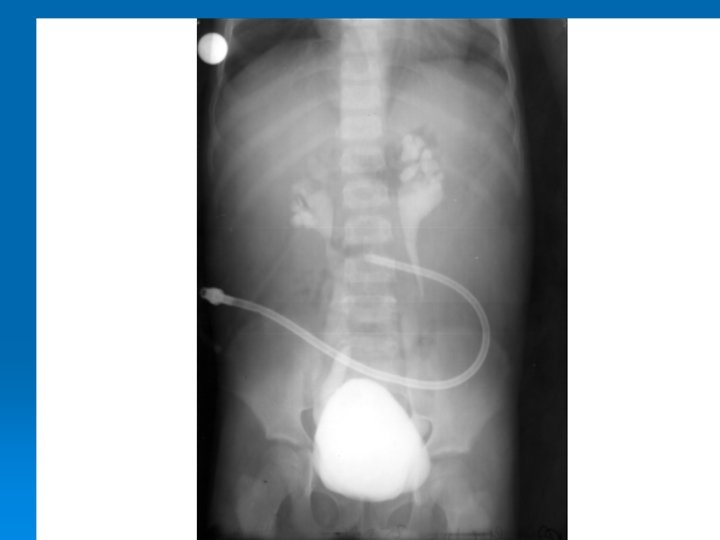

Çocukluk Çağında İdrar Yolu Enfeksiyonları İZLEMDE TANISAL GÖRÜNTÜLEME YÖNTEMLERİ Ø Miksiyon sistoüretrografisi: Vezikoüreteral geri kaçış (VÜR) görüntülenir. Ø DMSA sintigrafisi: Skar görüntülenir. Ø IVP: Tıkanıklık görüntülenir. Ø DTPA sintigrafisi: Tıkanıklık, böbrek fonksiyonları bozuk hastalarda atılım fonksiyonlarını değerlendirilebilir.